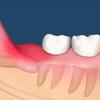

May 06, 16 · 但是对于智齿长歪、上下咬合不对位、经常发炎引起牙齿疼痛的智齿要及时的拔掉,尤其是对于智齿长歪侵犯邻牙的智齿是一定要拔掉的,如果长期不管,会导致健康的邻牙松动受损,到最后两颗牙齿都需要拔掉,这是得不偿失的。 长出来的智齿可以拔吗?Sep 25, · 随着科技进步,3c产品也越来越普及。而手机对现代人来说更是不可或缺。日前就有网友分享,自己将手机压在背后,睡醒时却发现手机「炸」开了Sep 25, 14 · 智齿长歪了肿么办? 来自 绵羊 长智齿本是好事,但是长歪了还发炎就真要人命了 左脸肿了一大片,吃东西也不舒服 也不太敢刷牙 该如何是好?

為什麼牙齦又腫又痛 牙齦腫脹的7大原因 別再怪到火氣大頭上 妳的煩惱顧問 Trouble Care

為什麼智齒會引起口臭 每日頭條